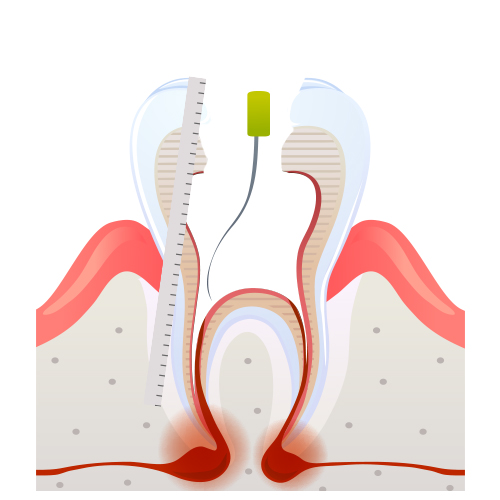

신경치료 과정

03

03

신경제거 및 길이측정